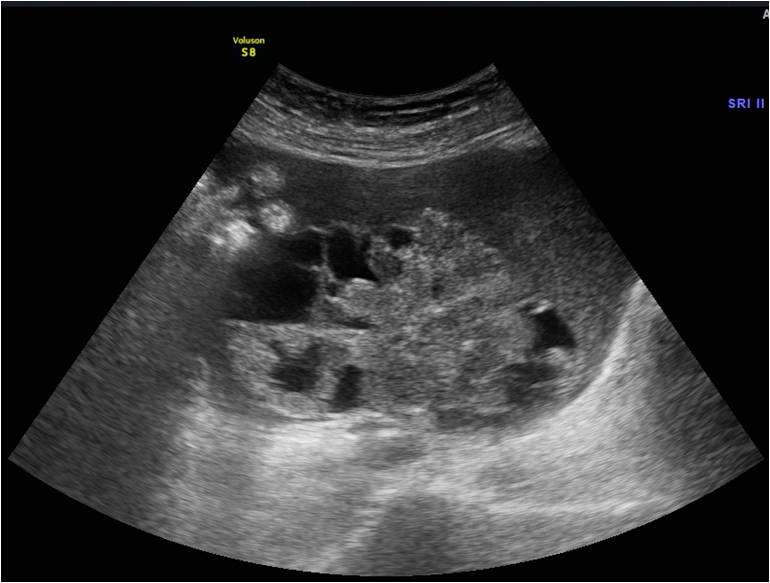

子宫内膜癌,子宫粘膜下肌瘤b超表现

4、卵巢癌

卵巢深藏盆腔,即便长肿瘤都不容易发现。卵巢癌早期以腹胀症状,无特异性,多数卵巢癌女性以为是肥胖引起的腹胀。

双侧卵巢癌

作为常见的女性肿瘤,随着年龄增长,尤其是更年期女性患卵巢癌最多。多见于停经之后,40-50岁之间,未生育或独身女性都应定期做好常规检查和复查。